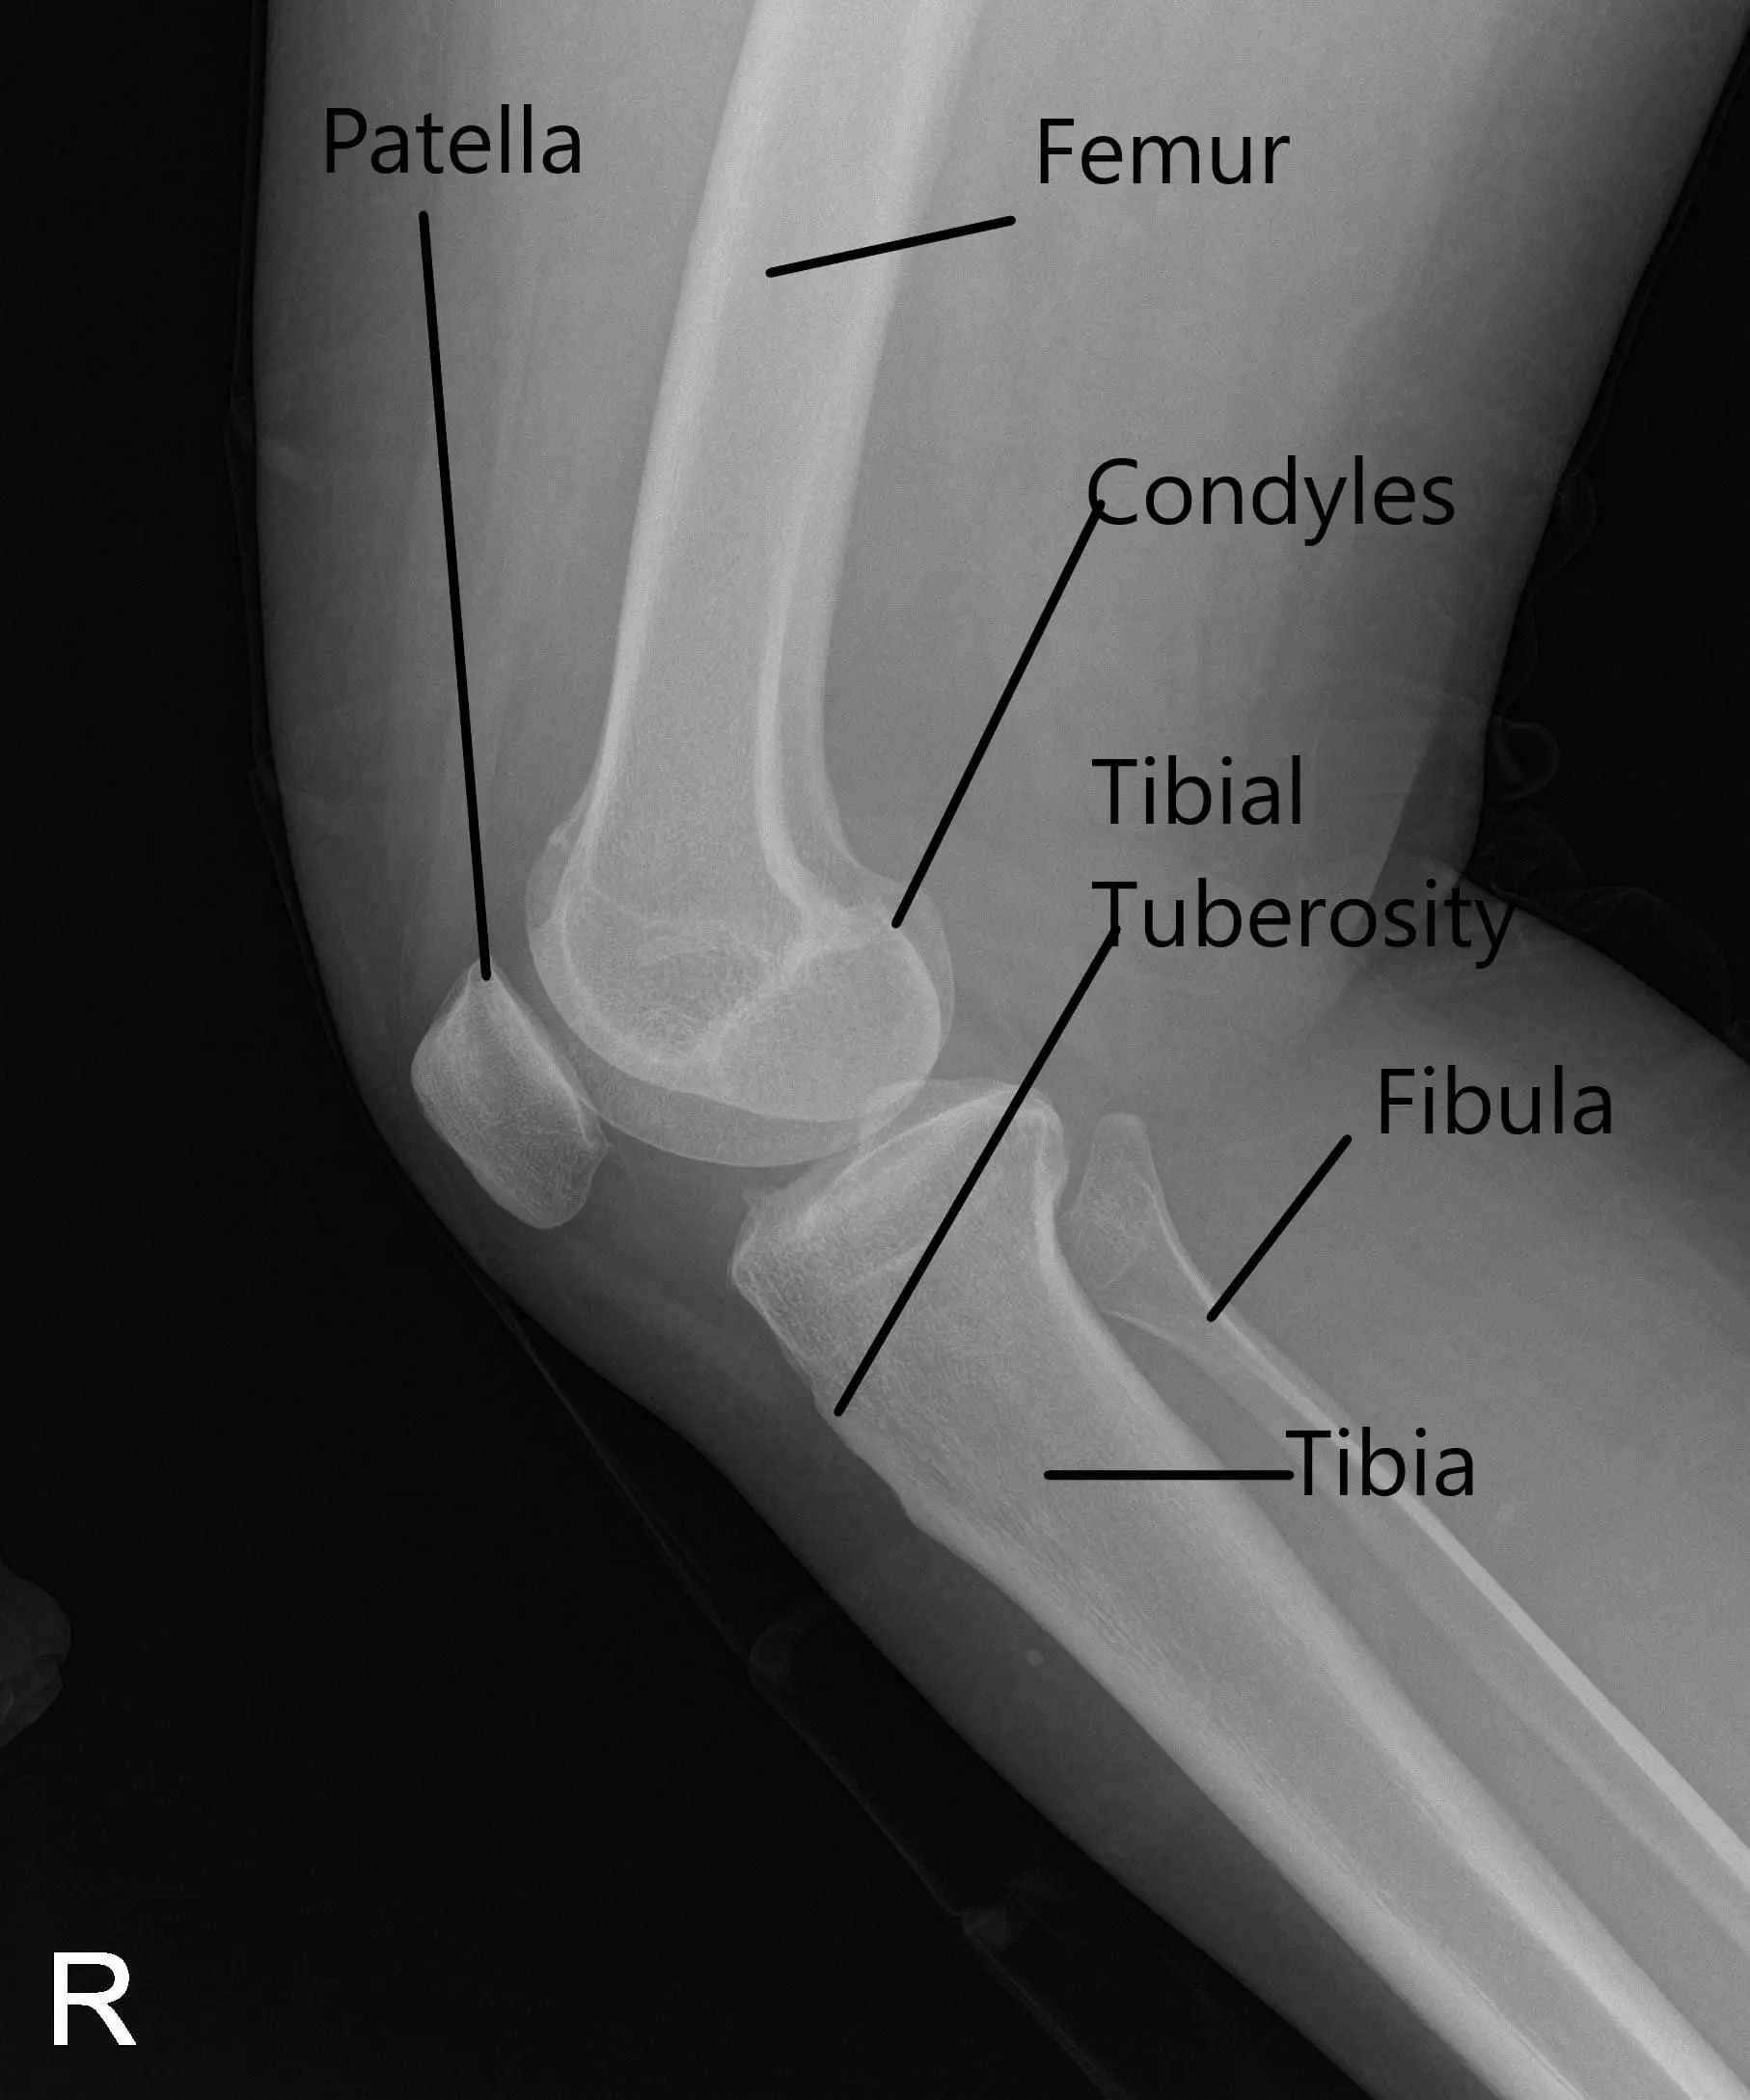

La radiografía de la rodilla derecha indicó osteoartrosis leve en el compartimento medial y anterior de la rodilla.

Se estableció un portal de entrada lateral y se examinó la articulación de la rodilla. Se encontró un desgarro periférico del menisco medial. También se encontró una lesión osteocondral de grado 1 a grado 2 en el cóndilo medial del fémur. El ligamento cruzado anterior presentaba algo de desgaste y degeneración.

No había lesión en el menisco ni en el fémur lateral ni en el cóndilo. Se inspeccionó la articulación patelofemoral y se encontró en buen estado. Ahora se realizó la reparación del menisco medial. Se usaron suturas FasT-Fix. Se utilizaron siete suturas para fijar la rotura periférica desde el cuerno posterior hasta la mitad del cuerpo.